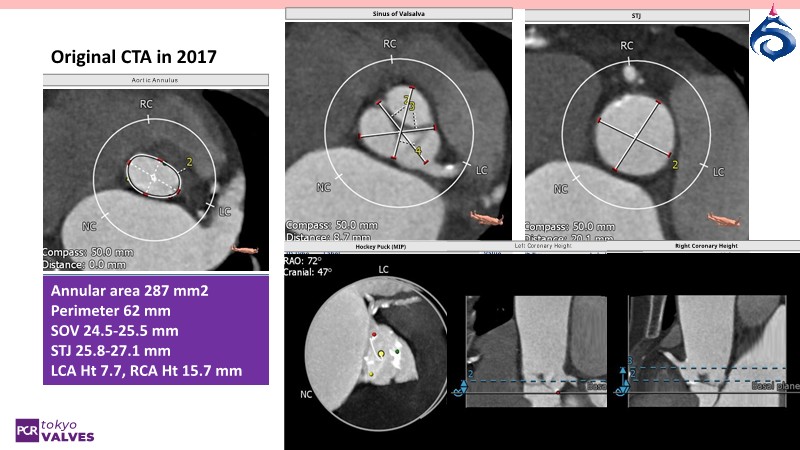

Watch this expert-led session on the latest Evolut TAVI advancements, device selection for small annulus cases, and strategies for complex anatomies. Learn about redo-TAVI feasibility and key 1-year data from the SMART trial.

• To understand the evidence and appreciate the importance of device choice in managing patients with small annulus anatomy

• To master implantation techniques and discern the latest technological evolutions for treating patients with complex anatomies